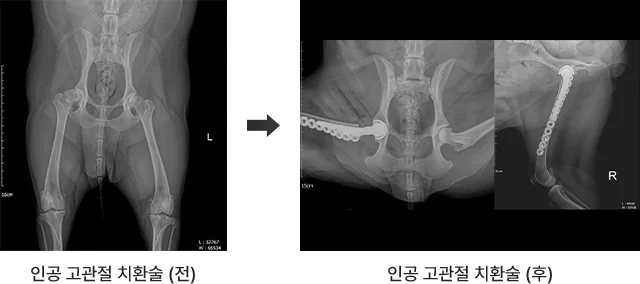

1. 인공 고관절 치환술

고관절 이형성증, 고관절 탈구, 이차적 골관절염 등으로 인해 파행이 심하고 통증이 지속되는 경우, 인공 고관절 치환술은 가장 근본적인 해결책이 됩니다.

아이가 걷는 기쁨을 되찾을 수 있도록, 리본의 THR 수술은 정밀도와 안정성에 집중합니다.

인공고관절치환술 전후 비교 사진